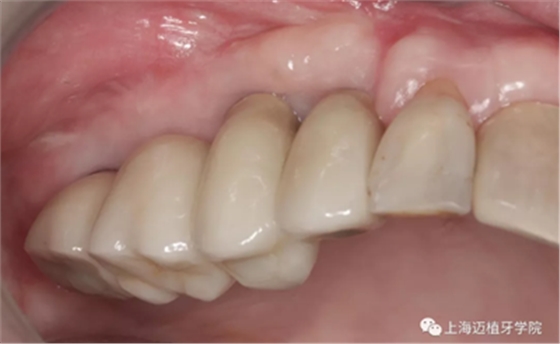

戴牙

GBR骨生物材料植骨失敗后,利用BBA植骨法及軟組織處理病例